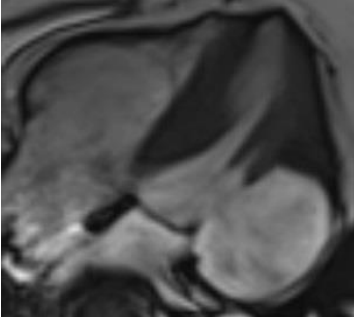

Despite electrolyte optimization, ventricular arrhythmias persisted, and he experienced bradycardia episodes( Figure 2,3). An echocardiogram( Figure 4) revealed cardiac abnormalities, including an aneurysmal basal posterolateral segment, akinesis in various segments, and a reduced ejection fraction. Cardiac MRI (Figure 5) was subsequently performed and showed a wide-necked out pouching from the basal anterolateral and inferolateral left ventricular wall. This was associated with myocardial thinning, severe dyskinesia, and near transmural sub-endocardial late gadolinium enhancement, resembling ischemia more than sarcoidosis.

Figure 4 Transthoracic echo (TTE) showing an aneurysmal basal posterolateral segment.

Figure 5 Cardiac MRI (CMR) showing outpouching from the basal anterolateral and inferolateral left ventricular wallwith associated myocardial thinning, severe dyskinesia and near transmural sub-endocardial late gadolinium enhancement.